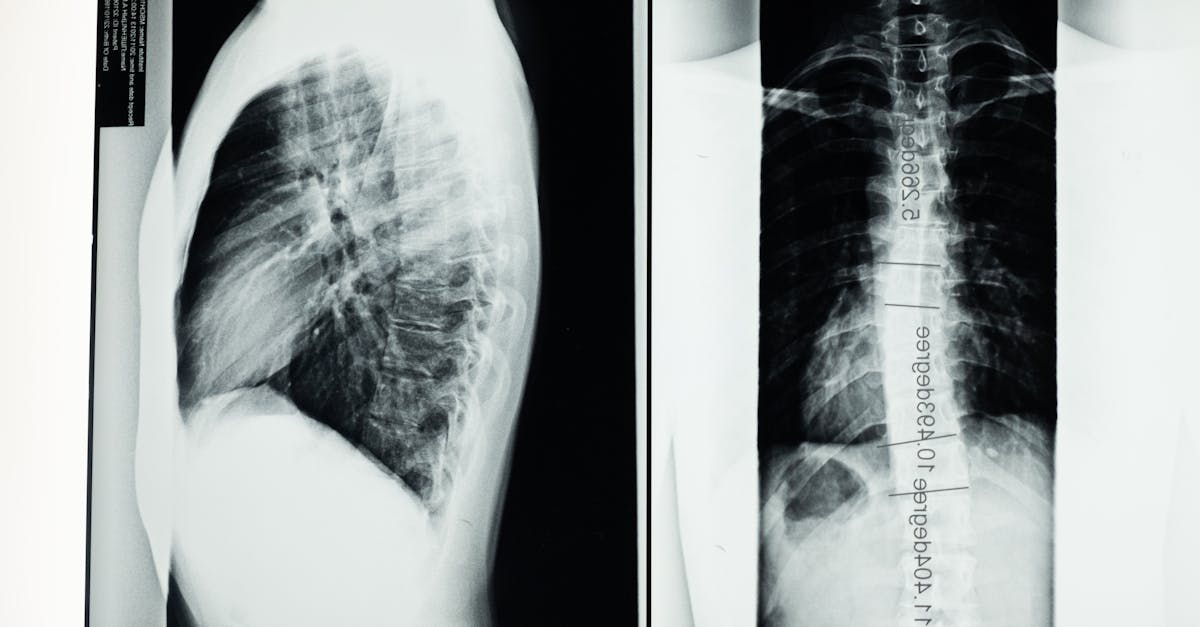

3. Hyperkyphosis - When the Spine Curves Beyond Normal Limits

Thoracic hyperkyphosis, commonly referred to as excessive upper back curvature or "hunchback," represents a significant postural deviation that profoundly impacts both structural integrity and functional capacity of the spine. Normal thoracic kyphosis ranges between 20-40 degrees, but when this curvature exceeds 50 degrees, it creates substantial biomechanical dysfunction and increases the risk of multiple musculoskeletal conditions. Research has identified both structural and postural forms of hyperkyphosis, with the latter being more responsive to conservative intervention. The condition results from a combination of factors including prolonged flexed posturing, osteoporotic vertebral compression fractures, muscle imbalances, and genetic predisposition. Biomechanical studies reveal that excessive thoracic kyphosis significantly increases compressive forces on anterior vertebral bodies while creating excessive tension in posterior spinal structures, leading to accelerated disc degeneration and facet joint arthritis. The postural consequences extend beyond the thoracic region, as hyperkyphosis typically triggers compensatory cervical hyperextension and lumbar hyperlordosis to maintain horizontal gaze and overall balance. Clinical research has established strong correlations between thoracic hyperkyphosis and reduced pulmonary function, with severe cases showing up to 30% reduction in vital capacity due to chest wall restrictions. Additionally, individuals with hyperkyphosis demonstrate increased fall risk, reduced quality of life scores, and higher rates of vertebral fractures. Evidence-based interventions focusing on thoracic extension mobility, postural muscle strengthening, and spinal alignment awareness have shown remarkable success in reducing kyphotic angles and improving associated symptoms.